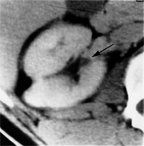

Serial CT image of renal cell carcinoma with growth in VHL demonstrates a subtle lesion deep in the renal parenchyma (arrow).